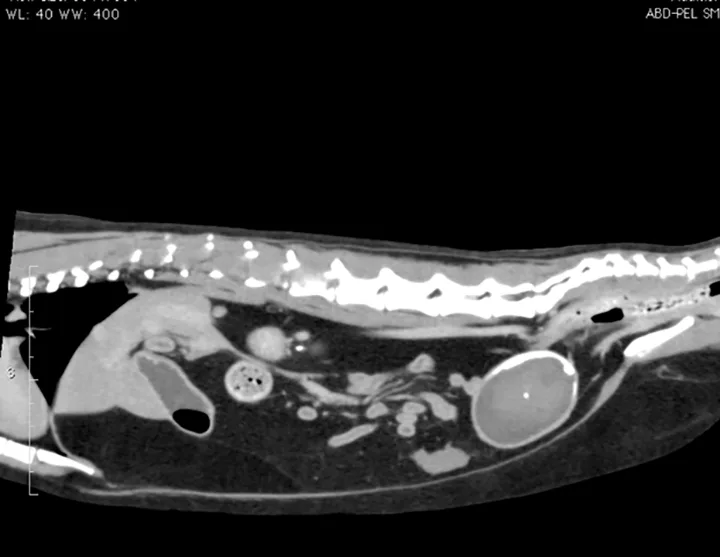

Figure 1. The urinary bladder appears large and there is bilateral renomegaly in this right lateral view; dystrophic mineralization is present in the right kidney.

At initial examination, Ivan was alert and responsive with heart rate, respiratory rate, and temperature within normal limits. He was estimated to be 5% dehydrated and had a large, firm, nonexpressible bladder. He was sedated with 0.015 mg/kg IV of buprenorphine, 0.2 mg/kg IV of midazolam, and administered a total of 2.5 mL of propofol IV for urinary catheter placement. A 5-French red rubber catheter was placed with slight resistance and maintained in place with butterfly tape and stay sutures. A CBC, serum chemistry panel, and plain abdominal radiographs (Figure 1) were performed.